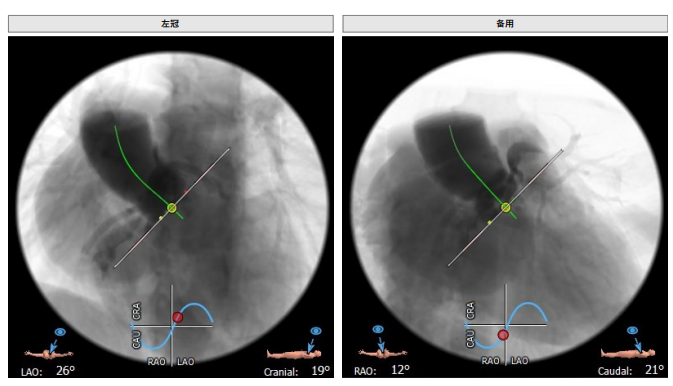

工作体位:LAO:12°CRA:5° ;左冠切线位:LAO:26° CRA:19°